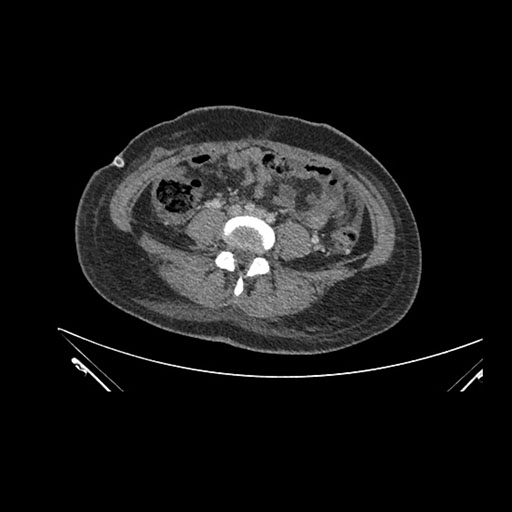

Imaging Analysis

Look through the patient's CT scan to identify any areas of concern for the necessary procedure.

Axial Venous

Based on initial findings, which issue(s) would you be most concerned about?